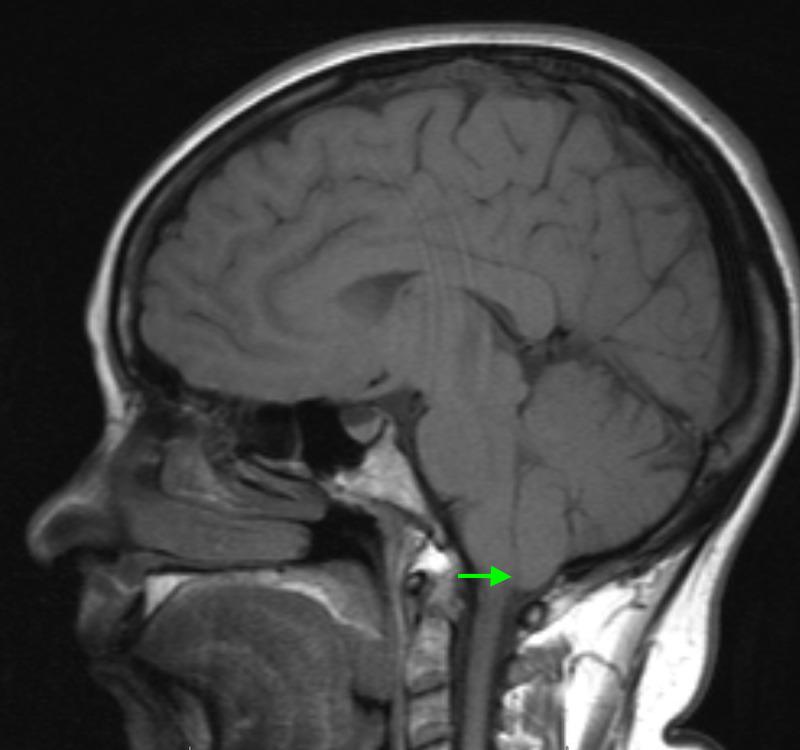

Epidural analgesia is an efficient method of controlling pain and has a wide spectrum of therapeutic and diagnostic applications. Potential complications may occur in a delayed fashion, can remain undiagnosed, and can be a source of significant morbidity. We present a 37-year-old woman presented with severe spontaneous occipital headaches, diplopia, and dizziness that occurred spontaneously six weeks after giving birth. Her primary method of pain control during labor was epidural analgesia. Her neurologic exam revealed a cranial nerve six palsy with ptosis, and her brain MRI demonstrated a Chiari I malformation which had not been previously diagnosed. CT myelography of the lumbar spine revealed extradural contrast extravasation within the interspinous soft tissue at L1-L2, which was the site of her prior epidural procedure. She underwent epidural blood patch administration, and her cranial nerve palsy resolved along with all of her other symptoms. The development of concurrent Chiari I malformation and cranial nerve palsy after epidural anesthesia is an exceptionally rare occurrence. Neurologic complications after epidural anesthesia are likely under-reported, since patients are often lost to follow-up or have subtle neurologic signs which can easily be missed. This frequently delayed presentation emphasizes the importance of patient education and the necessity of a detailed neurological exam when symptoms occur.

摘要

硬膜外镇痛是一种有效的疼痛控制方法,具有广泛的治疗和诊断应用。潜在并发症可能延迟出现,可能未被诊断出来,并且可能是严重发病的根源。我们报告一名37岁女性,在产后六周出现严重的自发性枕部头痛、复视和头晕。她分娩期间的主要疼痛控制方法是硬膜外镇痛。她的神经系统检查显示有动眼神经麻痹伴上睑下垂,脑部磁共振成像显示有I型Chiari畸形,此前未被诊断出。腰椎CT脊髓造影显示L1-L2棘突间软组织内硬膜外造影剂外渗,这是她之前硬膜外操作的部位。她接受了硬膜外血贴治疗,动眼神经麻痹以及其他所有症状均得到缓解。硬膜外麻醉后并发I型Chiari畸形和动眼神经麻痹极为罕见。硬膜外麻醉后的神经系统并发症可能报告不足,因为患者常常失访或有轻微的神经系统体征,很容易被漏诊。这种经常延迟出现的情况强调了患者教育的重要性以及出现症状时进行详细神经系统检查的必要性。